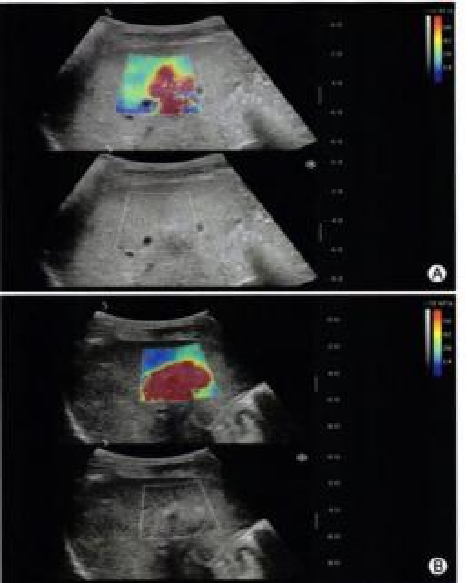

实时剪切波弹性成像

评估组织的软硬,并且提供定量数值,从而提示组织的良恶性。

image.png

鉴别诊断、精准分级、定量评价、穿刺引导、疗效评估、随访观察

恶性占位常常向周边组织进行侵润及扩散,二维很难观察到浸润部分的边界。使用实时剪切波成像能够对占位及周边组织进行硬度评估,通过颜色编码来区分不同组织的硬度信息,直观的观察占位组织的边界信息,更方便区分占位组织和正常组织的边界,准确评估消融范围。

左图病例所示:

钼靶阴性,B型发现非肿块病变

剪切波弹性成像见明确的硬度增高区域。

穿刺及手术病理结果:浸润性导管癌(IDC)

非肿块型病变:B型图像无法确认病变范围,E成像帮助发现异常区域和评估